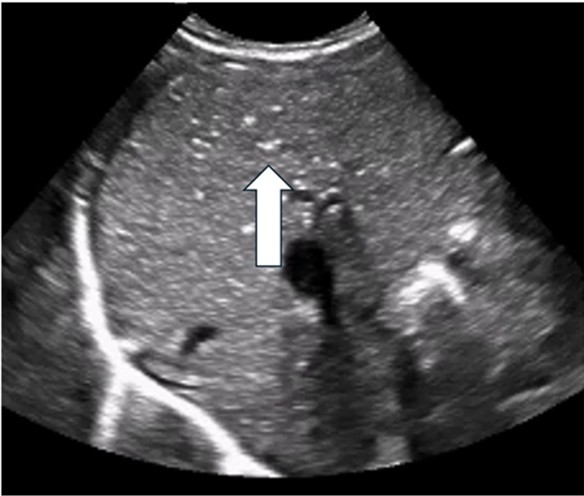

![]() |

Arrow indicates PVG identified as echogenic bubbles in the liver |